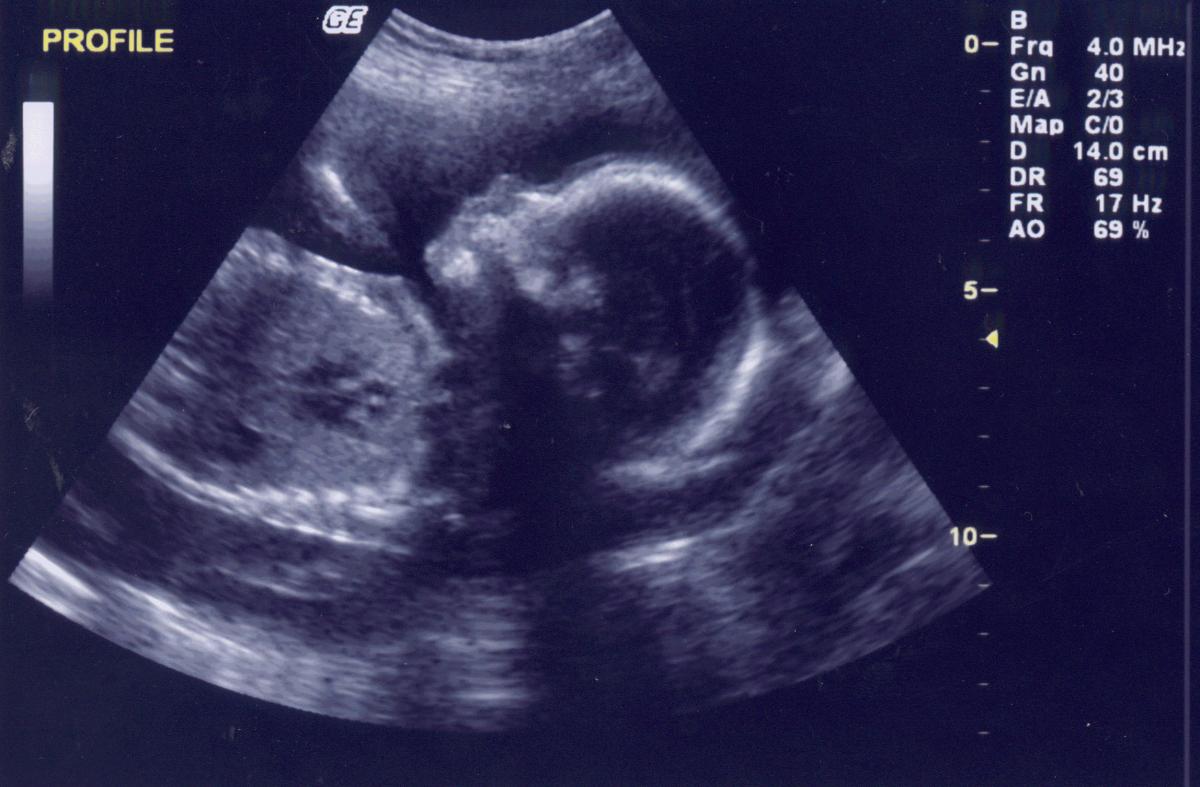

Kelly Lewis, o femeie în vârstă de 26 de ani din Marea Britanie, a avut parte de o surpriză de proporţii după ce și-a făcut o ecografie 4D în timpul sarcinii.

În imagine, lângă făt, apare o siluetă foarte asemănătoare cu a unui înger. Atât viitoarea mămică, cât şi medicii, au rămas fără cuvinte.

Kelly şi soţul ei mai au un copil şi au mărturisit că pe ecografiile cu acesta nu au semnalat nicio imagine care să îi pună pe gânduri.